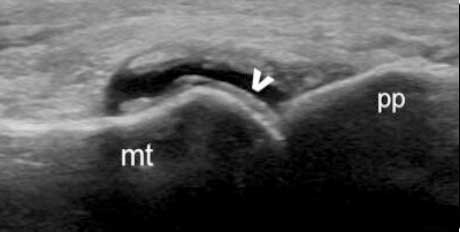

肌骨超声可通过高清影像图判定软骨表面有无出现一条与强回声骨皮质平行的线样强回声,即“双轨征”这一痛风性关节炎特征性表现,判定疾病所属。当尿酸盐粘附并沉积于漂浮的滑膜上时,超声检查可在关节腔内发现漂浮的高亮回声;而当尿酸盐长期沉积于韧带上时,在超声中即显示条带状的略高回声(韧带)中出现高回声点、高回声带或高回声团块(尿酸盐),从而判断痛风病情处于哪一时期。

“双轨征”

跖趾关节软骨表面可见高回声不规则增强的软骨滑膜边缘线,呈“双轨征”。

高回声带

软骨表面回声增强,与深面的骨性关节面强回声线形成“双轨征”。